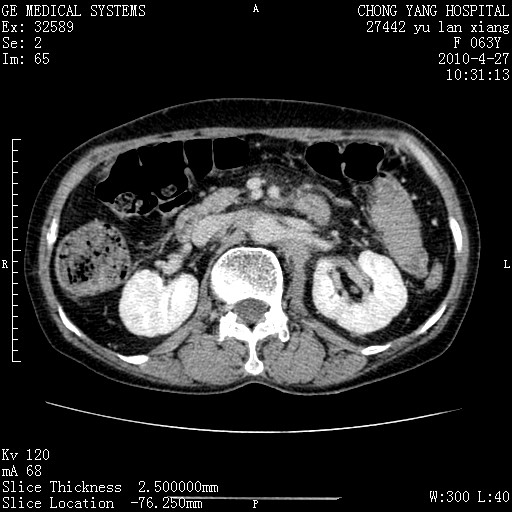

标题: CT26066:F63Y 上腹正中压痛半月,CA199:7400u/ml,MR示胰腺炎伴 [打印本页]

胰腺癌侵犯腹腔动脉干-分支、胃壁、左侧膈肌伴胰周及腹膜后淋巴结转移、胆囊切除术后。

胰腺癌侵犯腹腔动脉干-分支、胃壁、左侧膈肌伴胰周及腹膜后淋巴结转移、胆囊未显影。